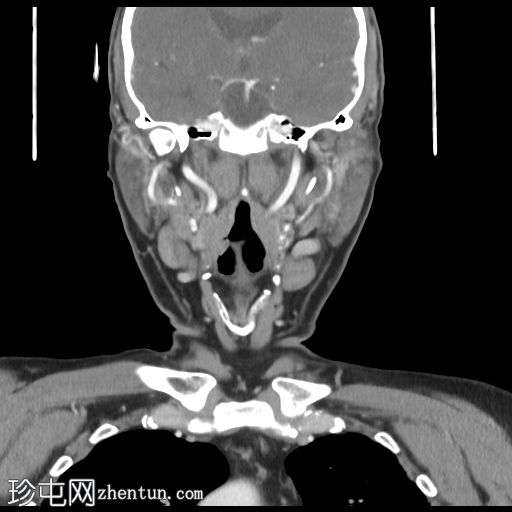

轴位增强扫描(门静脉期)

食管下段可见巨大管腔内肿块。

食管周围、隆突下及气管旁可见多个肿大淋巴结。左侧食管上段旁、气管食管沟处可见一个远处巨大淋巴结,可能影响左侧喉返神经

左侧声带外展(部分成像),屏气扫描时对侧声带代偿性向内侧弯曲,符合左侧声带麻痹表现。